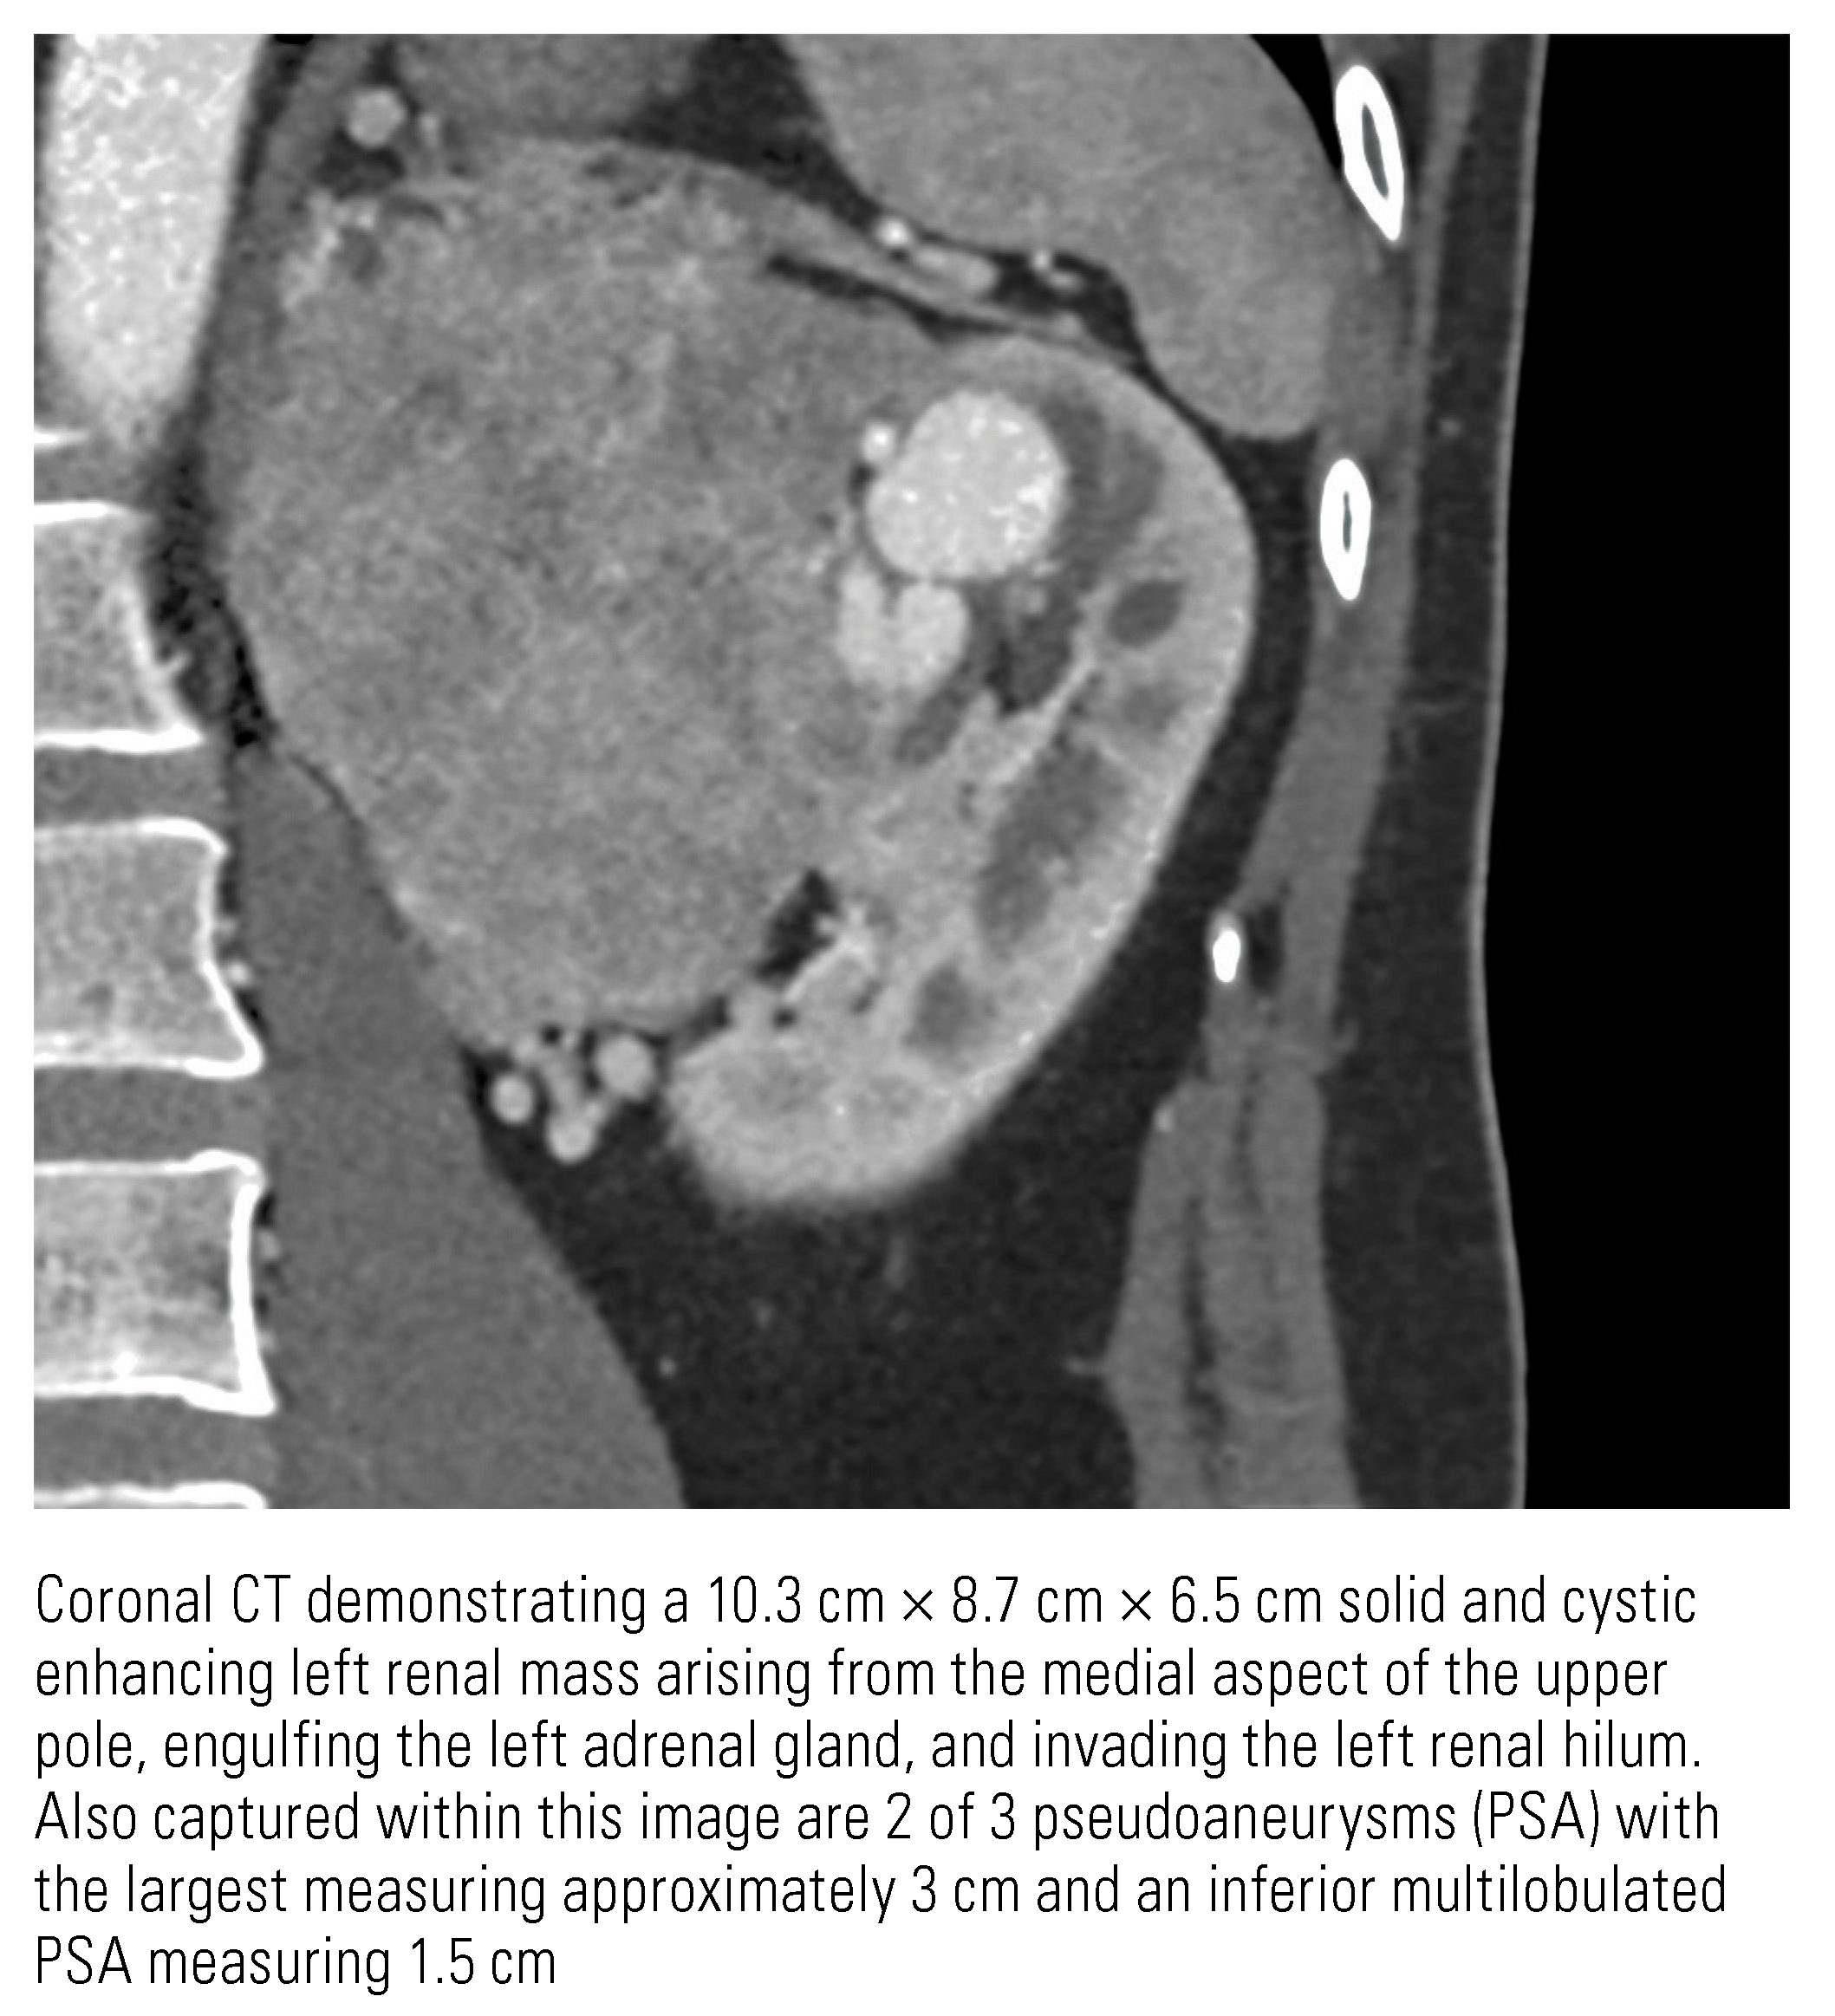

Renal Cell Carcinoma with Intratumoral Pseudoaneurysm